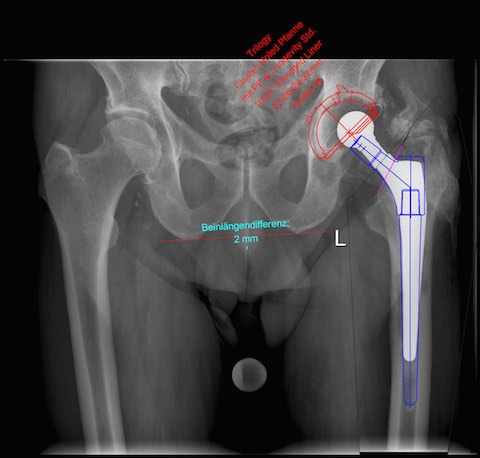

- Freitag T, Reichel H: Primäre Hüftendoprothetik – OP-Technik: Präoperative Planung; AE- Manual der Endoprothetik 2022 DOI: 10.1007/978-3-662-55485-2_79-1